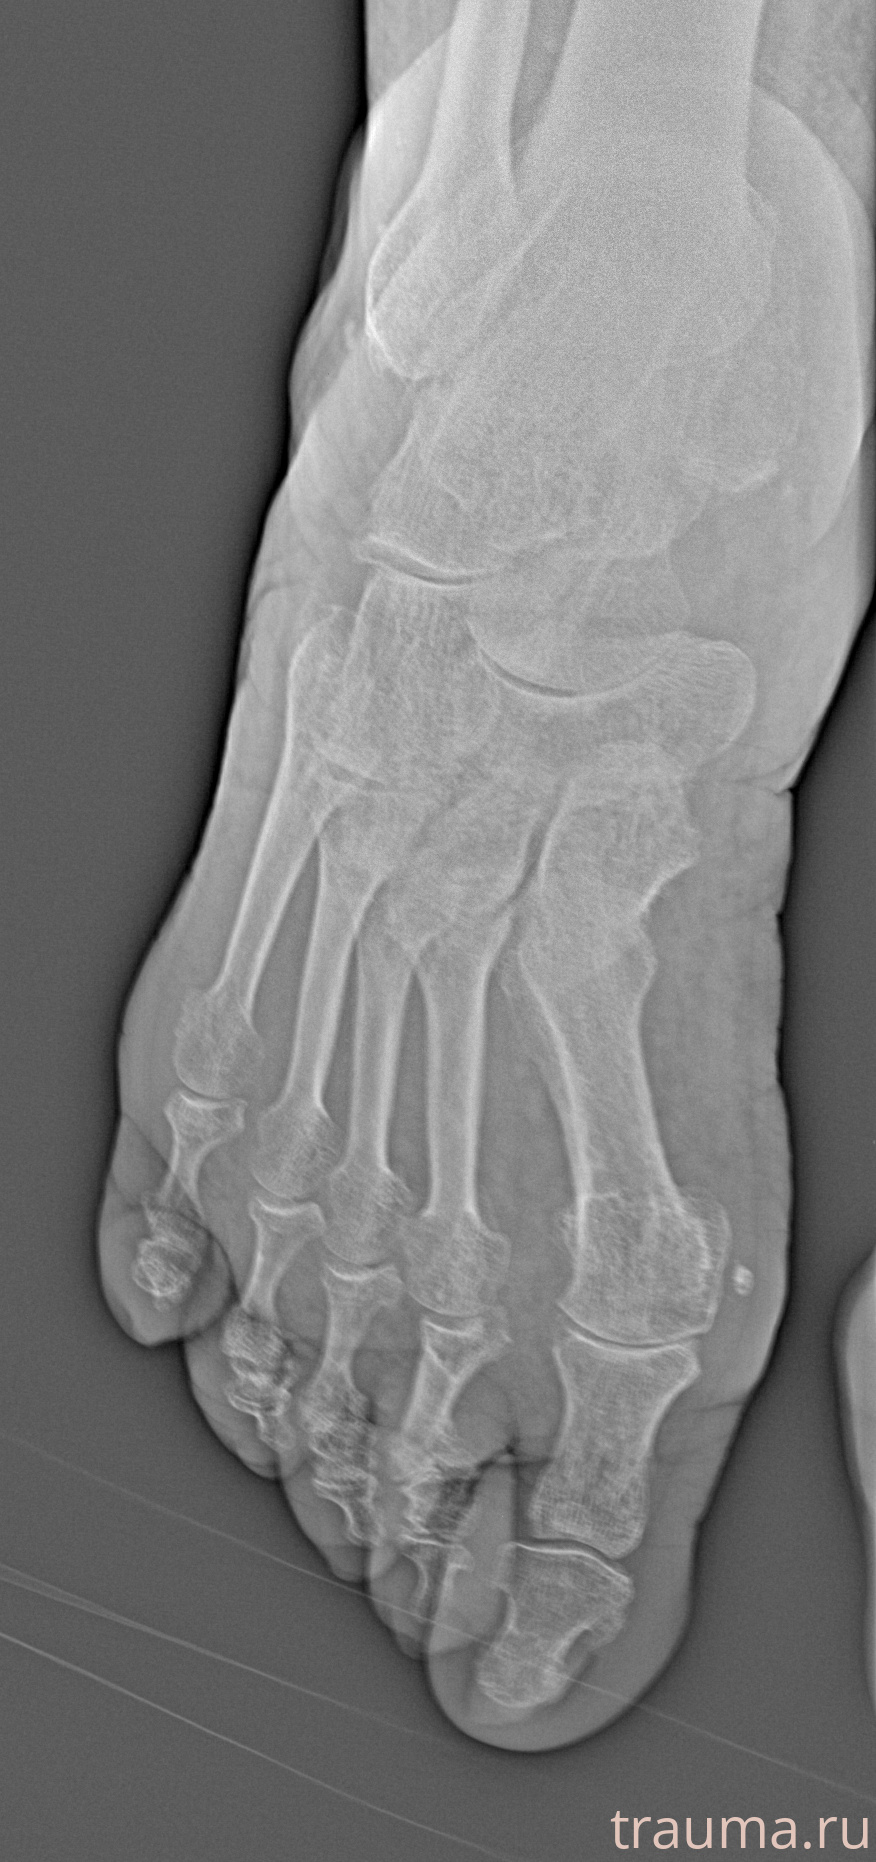

Рентген на дому: по вашему адресу приезжает врач-рентгенолог, травматолог-ортопед с мобильным рентгеновским аппаратом, проводит диагностику травмы или заболевания, делает необходимые рентгенограммы, дает рекомендации по дальнейшему лечению. Получить качественные снимки в домашних условиях возможно благодаря уникальной методике, разработанной МосРентген Центром для института  Склифосовского